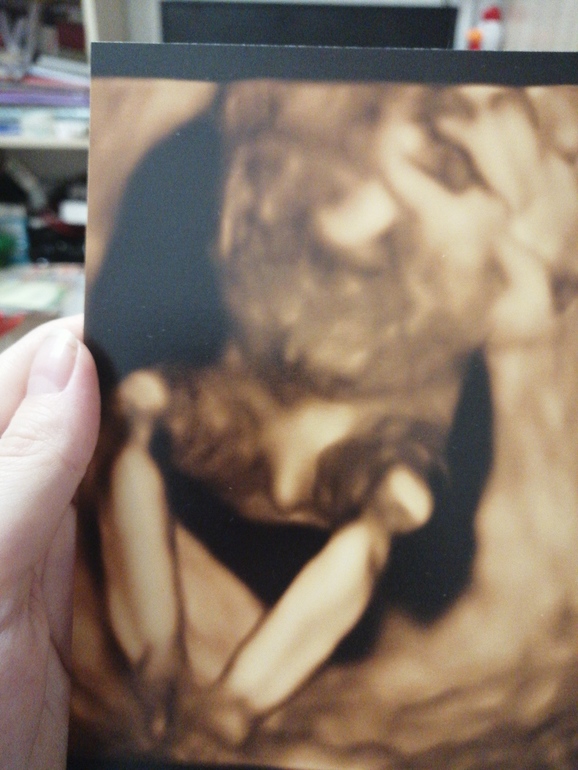

Была на 3д УЗИ в 15 недель, доктор четко увидела мальчика даже фотку дала, а обычное УЗИ да еще и 2 врача видят девочку🙄Вот и кому теперь верить?

Половой бугорок, ещё не до конца сформировавшийся. Смотрят с другого ракурса. Угол наклона этого бугорка. Так что, по вашему фото, ничего не понятно. Кто....

Наверное девочка, яичек не видно. Мне в 16 недель (1я беременность) кокушник показали, и они были внушительных размеров! ( по сравнению с писюном)

Да, я поняла. По фото вижу мальчика. Это я написала к тому, что до этого Вам говорили девочка, вполне легко могли ошибиться

Яичек не видно, похоже все таки девочка, посмотреть бы с низу, с другого ракурса.

Ну, мне тоже кажется, что мальчик 🤷♀️если я правильно всё понимаю по фото